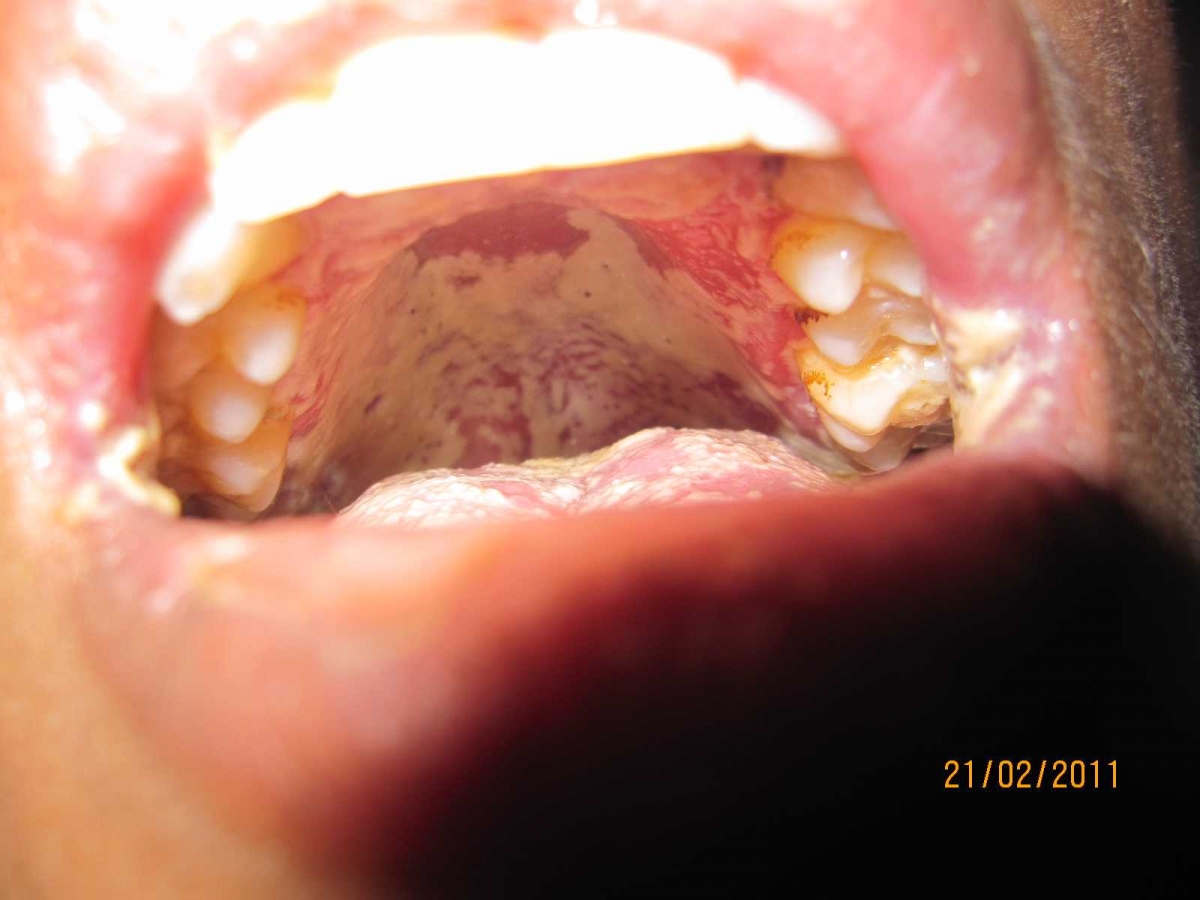

HIV AIDS Infeksi Jamur Rongga Mulut dan Masalah Sosial Sumber : www.kompasiana.com